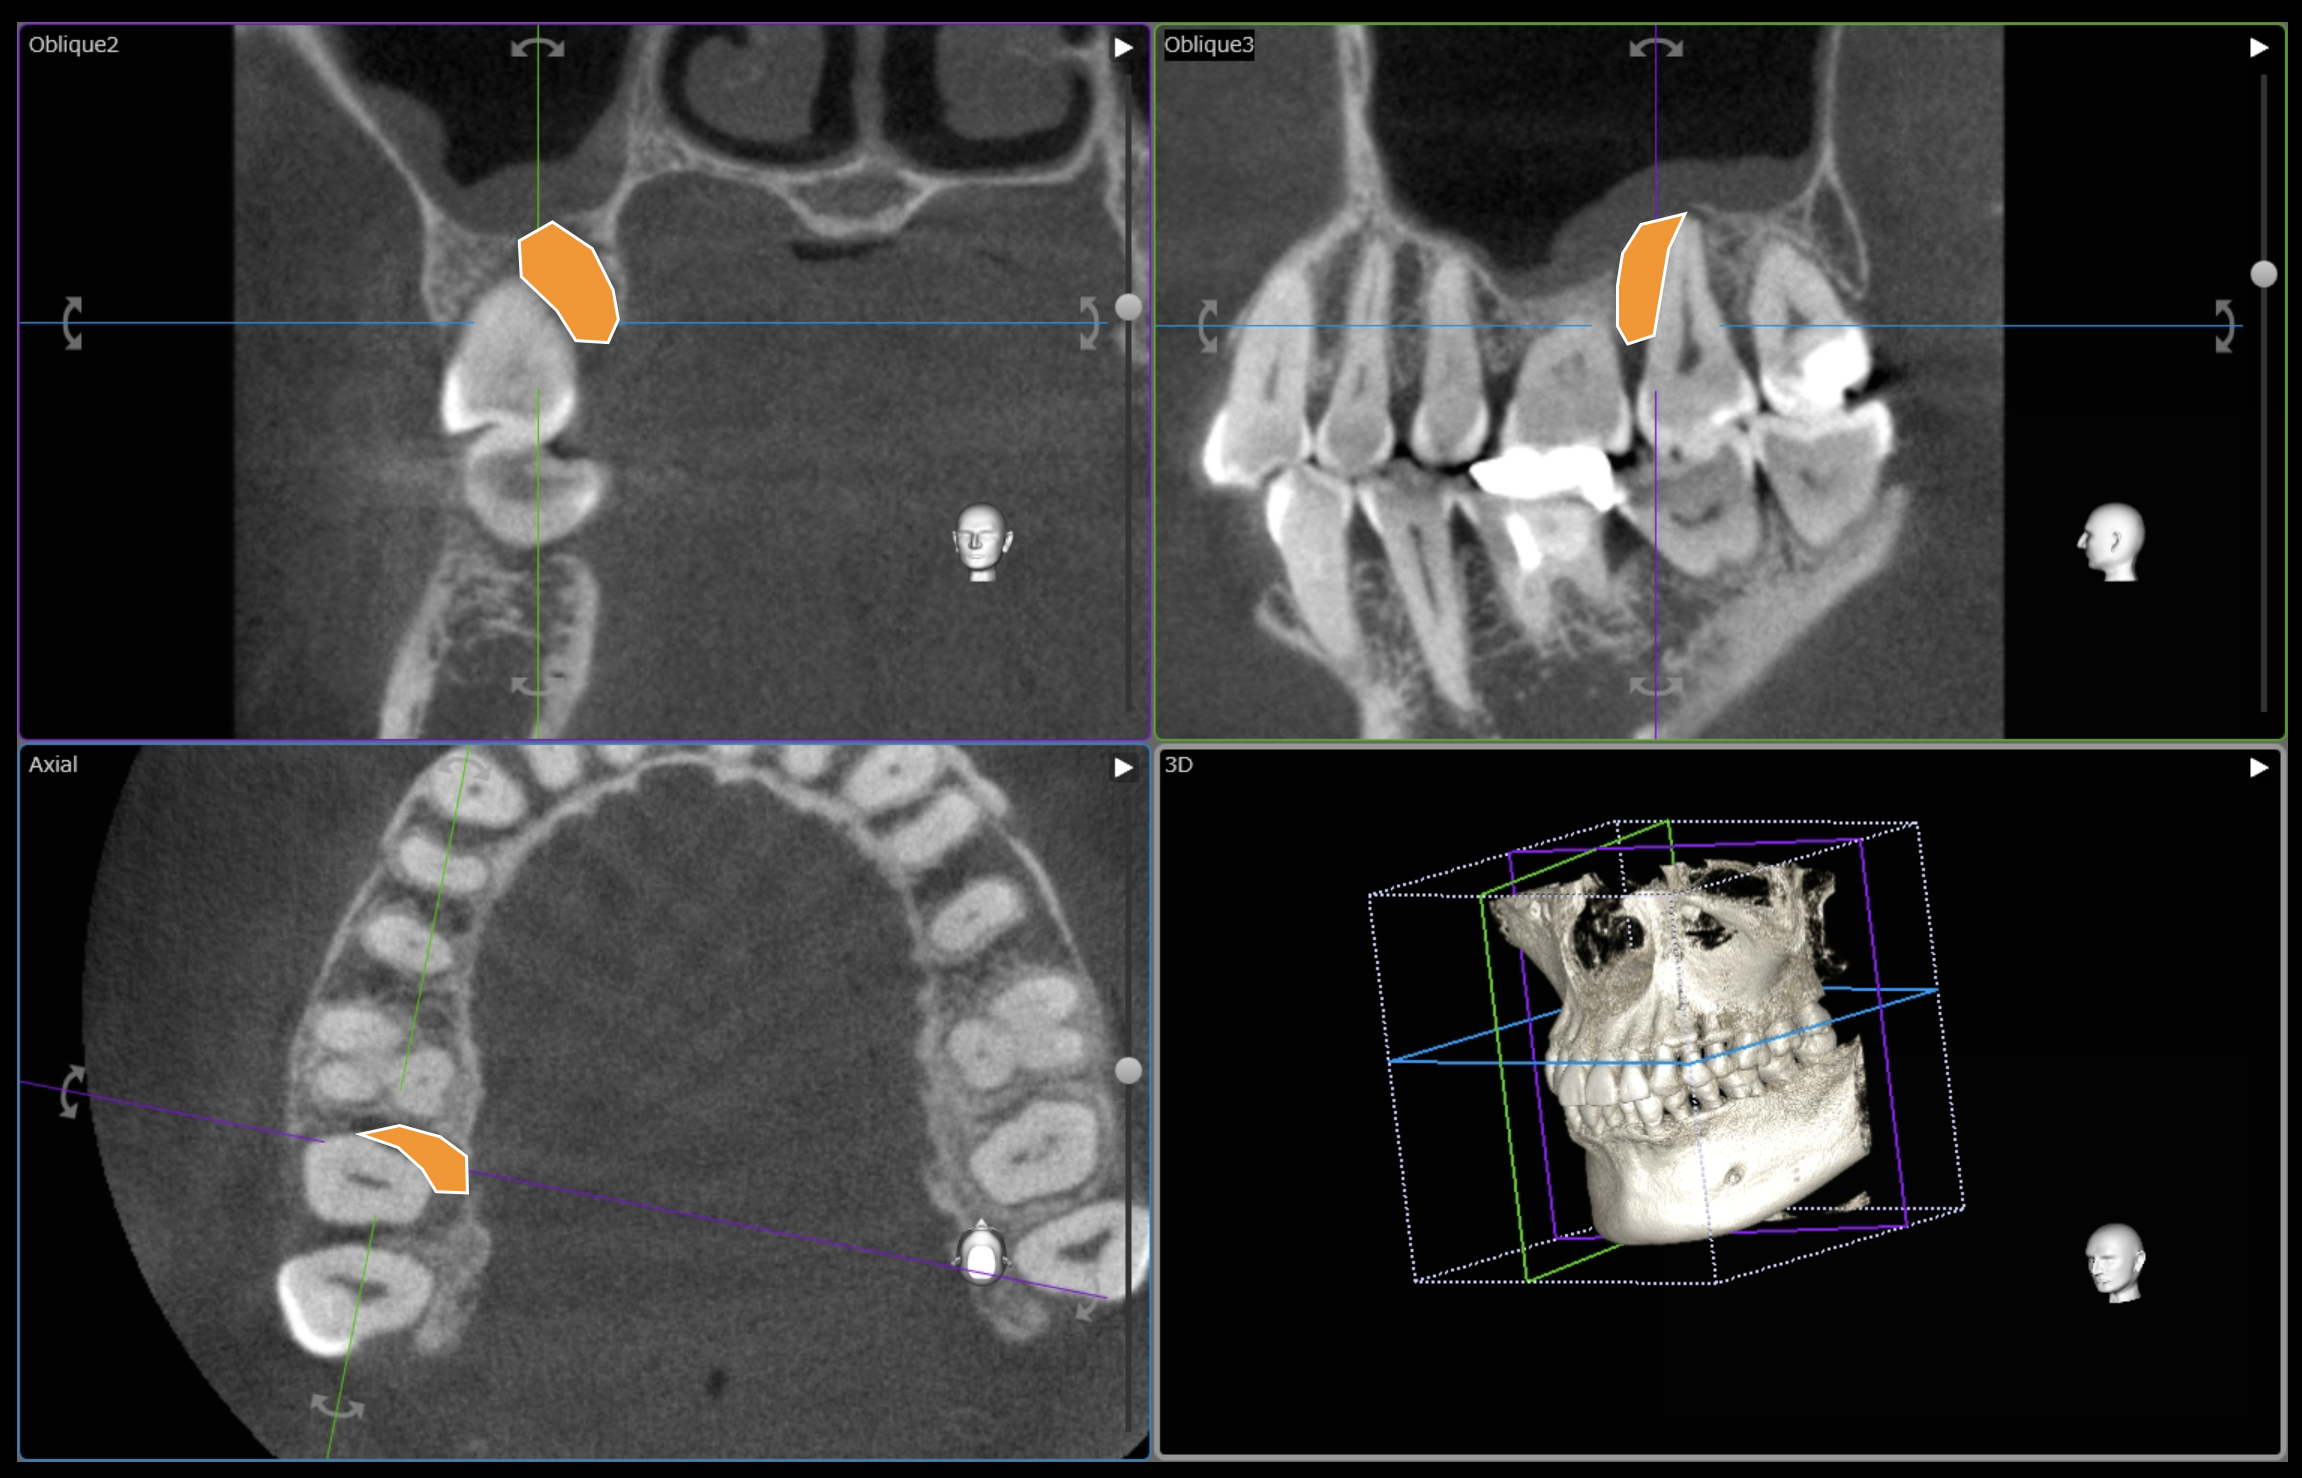

CT撮影を行うと、歯、骨が立体で描かれます。

また同時に、1本1本の歯をいろんな方向から見ることができます。

今回の右上の歯でいうと、

オレンジでマークしたところが黒く染まっているのがお分かりいただけるかと思います。

本来は白色〜鼠色で描かれ、骨があるべき部位です。

患者さんにも一目でお分かりいただけます、状態がわかれば、治療もスムーズに進みます。